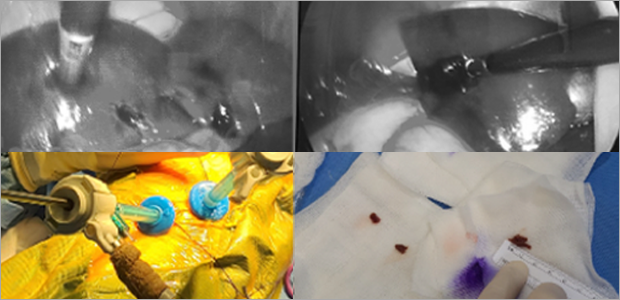

복강경 담낭절제술

케이스1

- 수술 1주차

- 수술 2주차

케이스2

- 수술 4일차

- 수술 3주차